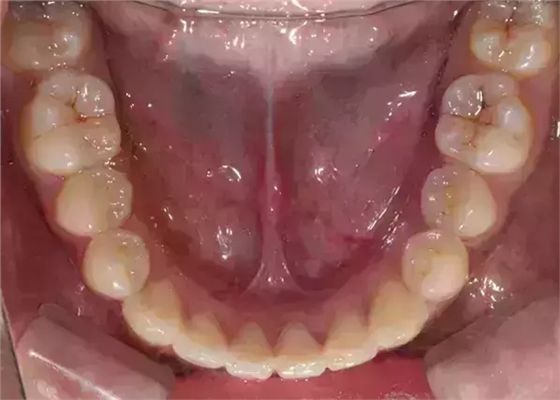

Damon 病例分享:安氏 II 類二分類露齦笑的矯治(董一磊)

上下牙列擁擠,磨牙尖牙Ⅱ 類關(guān)系,3 度的深覆牙合,上頜中切牙伸長內(nèi)傾拔除上頜雙側(cè)的第一前磨牙,先粘上頜高轉(zhuǎn)矩的自鎖托槽排齊牙列,唇向開展上頜切牙,有一定的覆蓋,粘下頜標準轉(zhuǎn)矩托槽,上頜 1, 2 之間植入種植支抗壓入,同時后牙 5, 6 之間植入種植支抗內(nèi)收前牙,打開咬合關(guān)閉間隙。治療關(guān)鍵:前牙轉(zhuǎn)矩的控制第 1 個月 上頜粘上 Damon Q 高轉(zhuǎn)矩托槽,上 .014 熱激活 NiTi 絲。第 3 個月 上換 .014 x .025 熱激活 NiTi 絲。第 5 個月 上頜基本排齊,覆蓋增大,上換 .017 x .025 NiTi絲,下頜粘托槽,下 .014 熱激活 NiTi 絲。第 7 個月 上 .017 x .025 NiTi 絲加搖椅,下?lián)Q .014 x .025 熱激活 NiTi 絲第 9 個月 上頜換 .019 x .025 NiTi 絲加搖椅,下頜換 .017 x .025 NiTi 絲第 11 個月 下頜換 .019 x .025 加搖椅,上頜 1, 2 之間, 5, 6 之間植入種植釘,下頜出現(xiàn)散隙。第 13 個月 上頜換 .019 x .025ss 加搖椅,前牙種植釘用 Power Chain 壓低前牙(每側(cè) 100g),后牙種植釘關(guān)閉間隙(每側(cè) 150g),下?lián)Q .019 x .025ss,Power Chain 關(guān)閉間隙。第 19 個月 上頜前牙基本壓低到位去除前牙種植釘,繼續(xù)用關(guān)閉間隙,下頜散隙關(guān)閉。

第 22 個月 上頜覆蓋變小,去除 5, 6 之間種植釘,后牙前移關(guān)閉間隙。第 30 個月 患者未配合中線牽引,下中線仍有 1mm 右偏,患者對矯治效果滿意要求拆除,拆除固定矯治器,取模制作壓模保持器。 1.骨性 Ⅱ 類的患者內(nèi)收前牙時需對上頜前牙的轉(zhuǎn)矩進行較好的控制才能獲得良好的面型和唇部形態(tài)。 2.露齦笑的患者治療前要分析其病因是唇、牙齦、牙齒、牙槽骨、上頜骨或多種因素結(jié)合,再制定矯治方案。 3.Ⅱ 類第二分類伴露齦笑的患者的上頜前牙移動軌跡是唇向開展-壓低-整體內(nèi)收。 4.Ⅱ 類第二分類牙齒舌傾比較厲害的情況,上頜中切牙慎用樹脂咬合墊。 5.壓低前牙或控根移動時容易發(fā)生牙根的吸收,需輕力緩慢的移動。